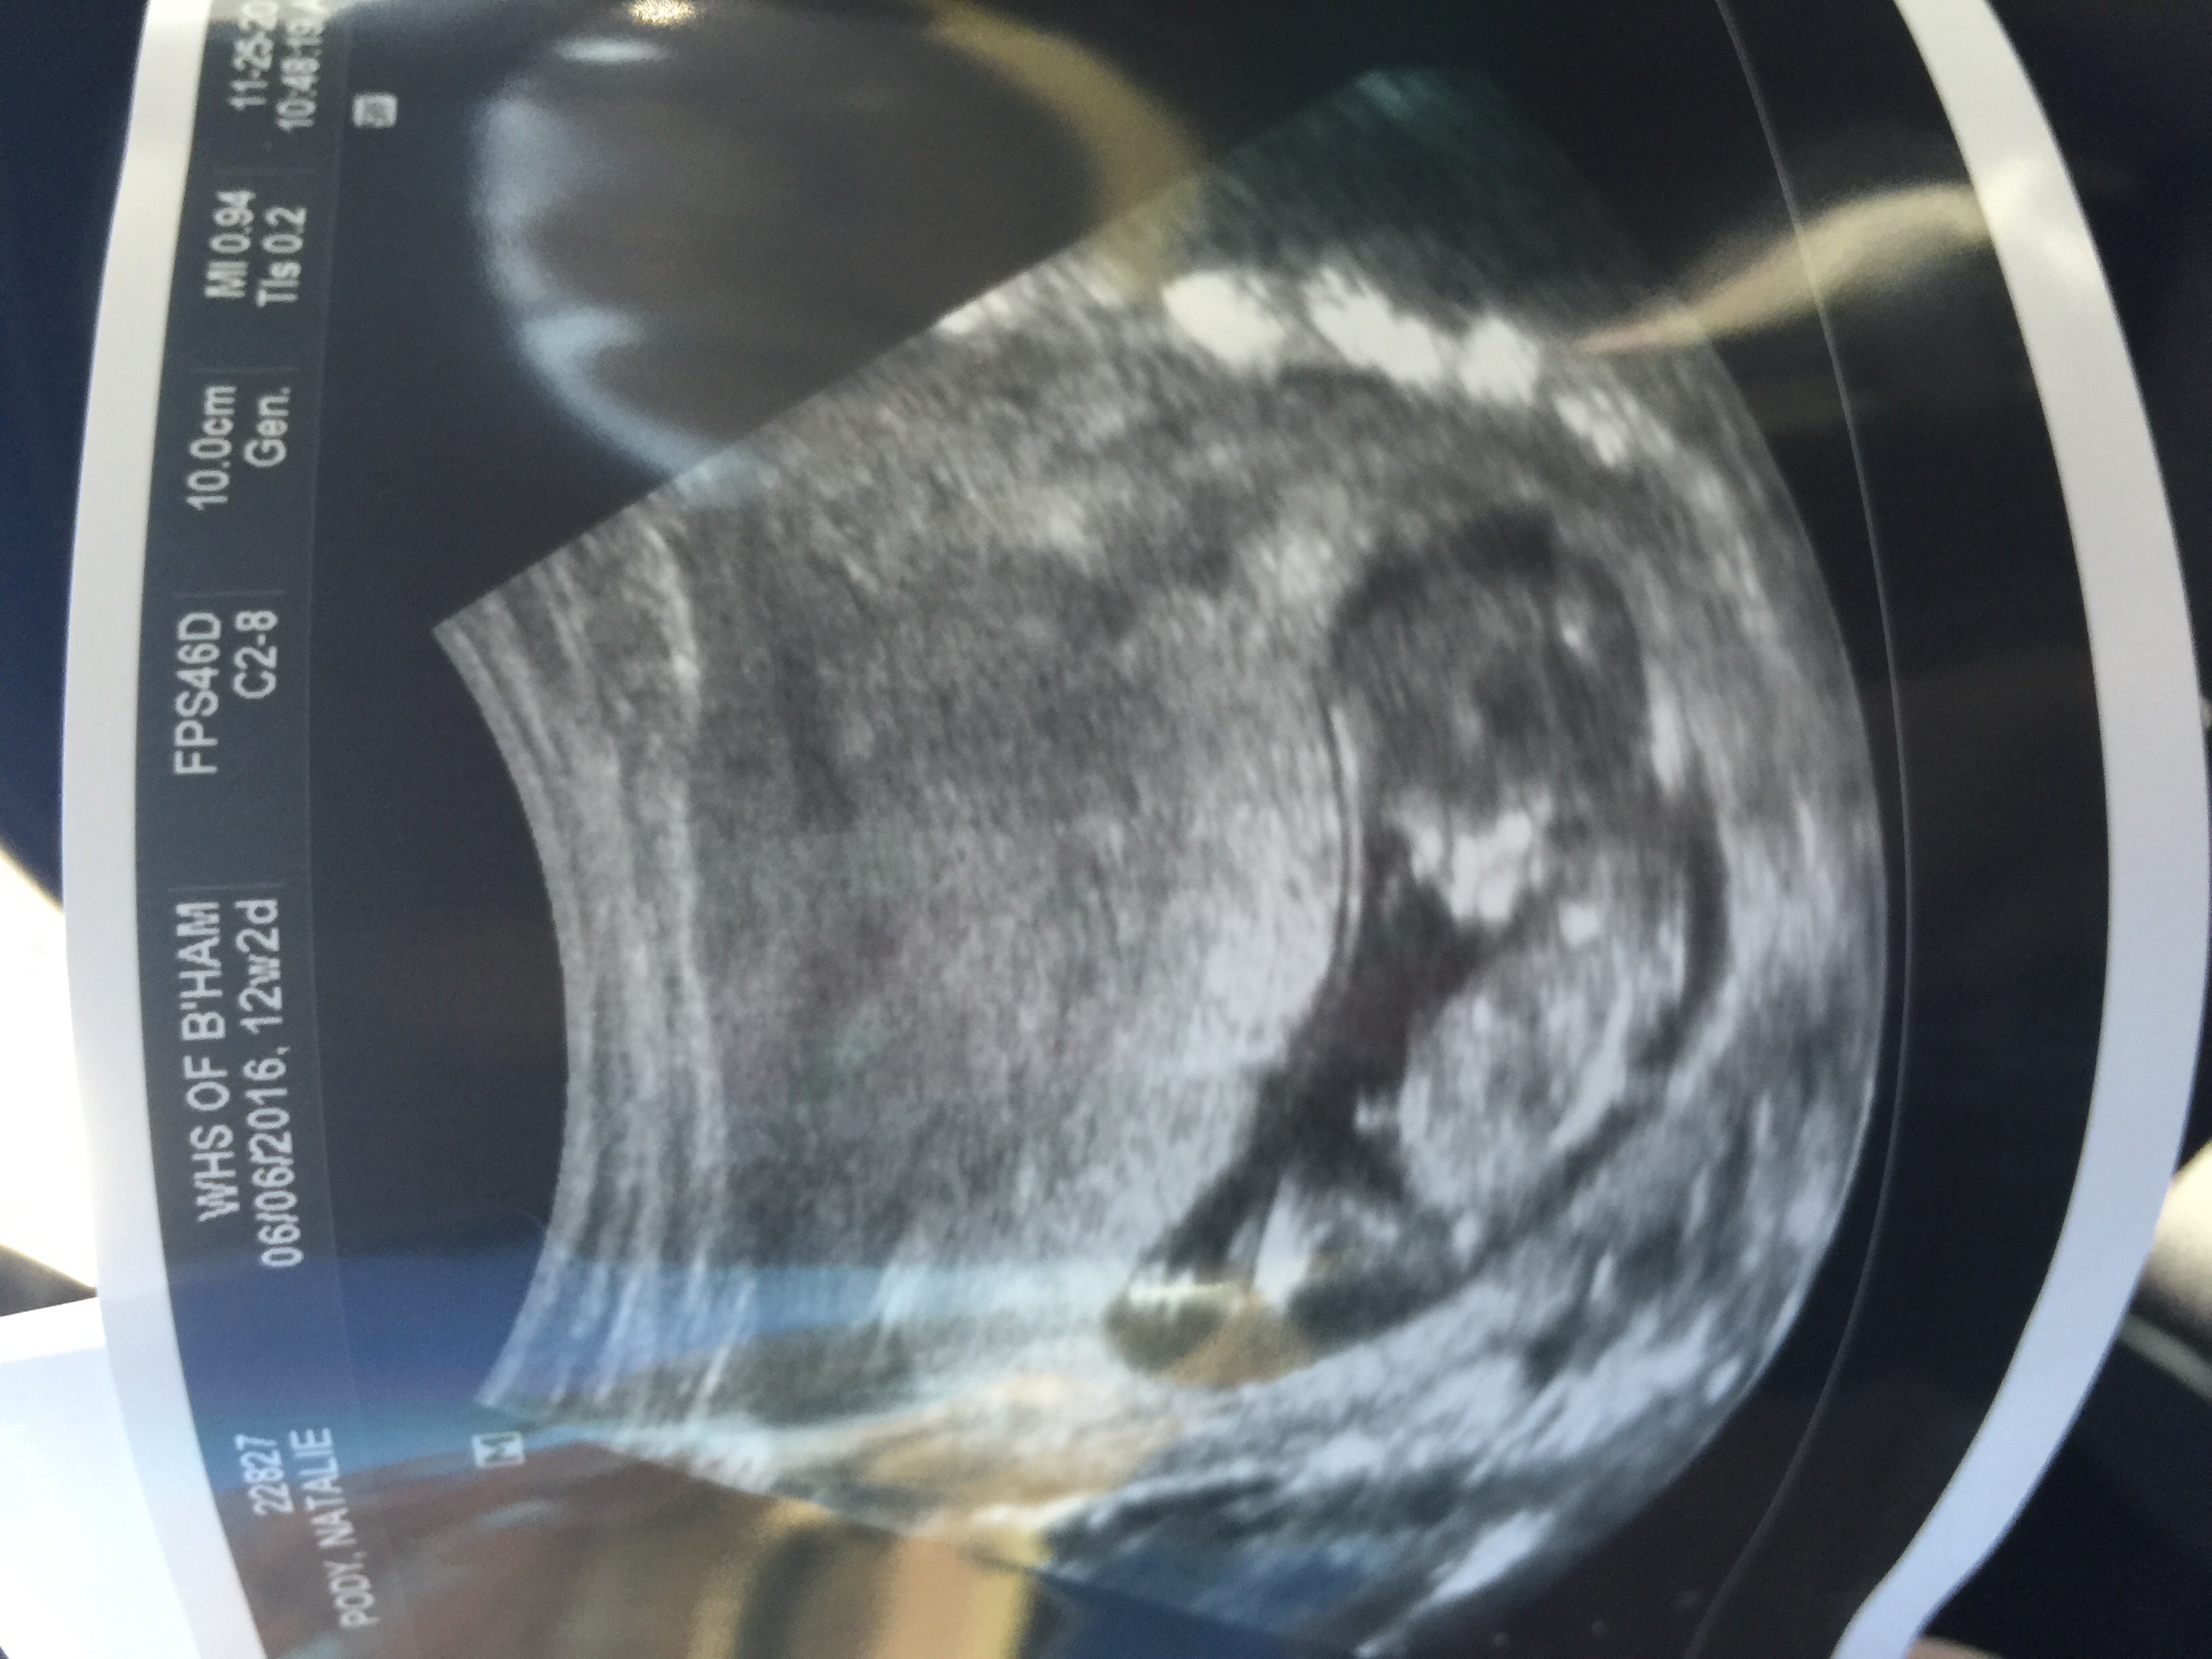

If this is even a nub!lol I'm only 12 and 2 so it's very early but just for fun! I do not care either way so share your guesses! She looked between the legs and didn't see anything but this looks like a blue nub to me. Attachment 28644

Another shot Attachment 28645